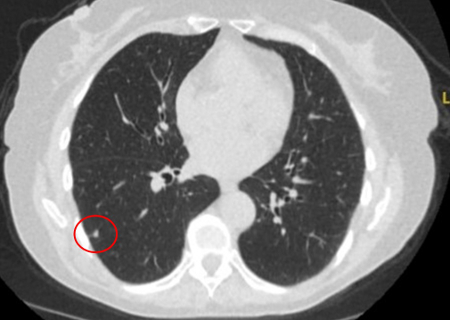

Computed tomography (CT) showing a small peripheral triangular nodule in the right lower lobe, consistent with an intrapulmonary lymph node

From the collection of Dr George Tsaknis, MD, PhD, FRCP(London), MRQA, MAcadMEd, PGCert; used with permission